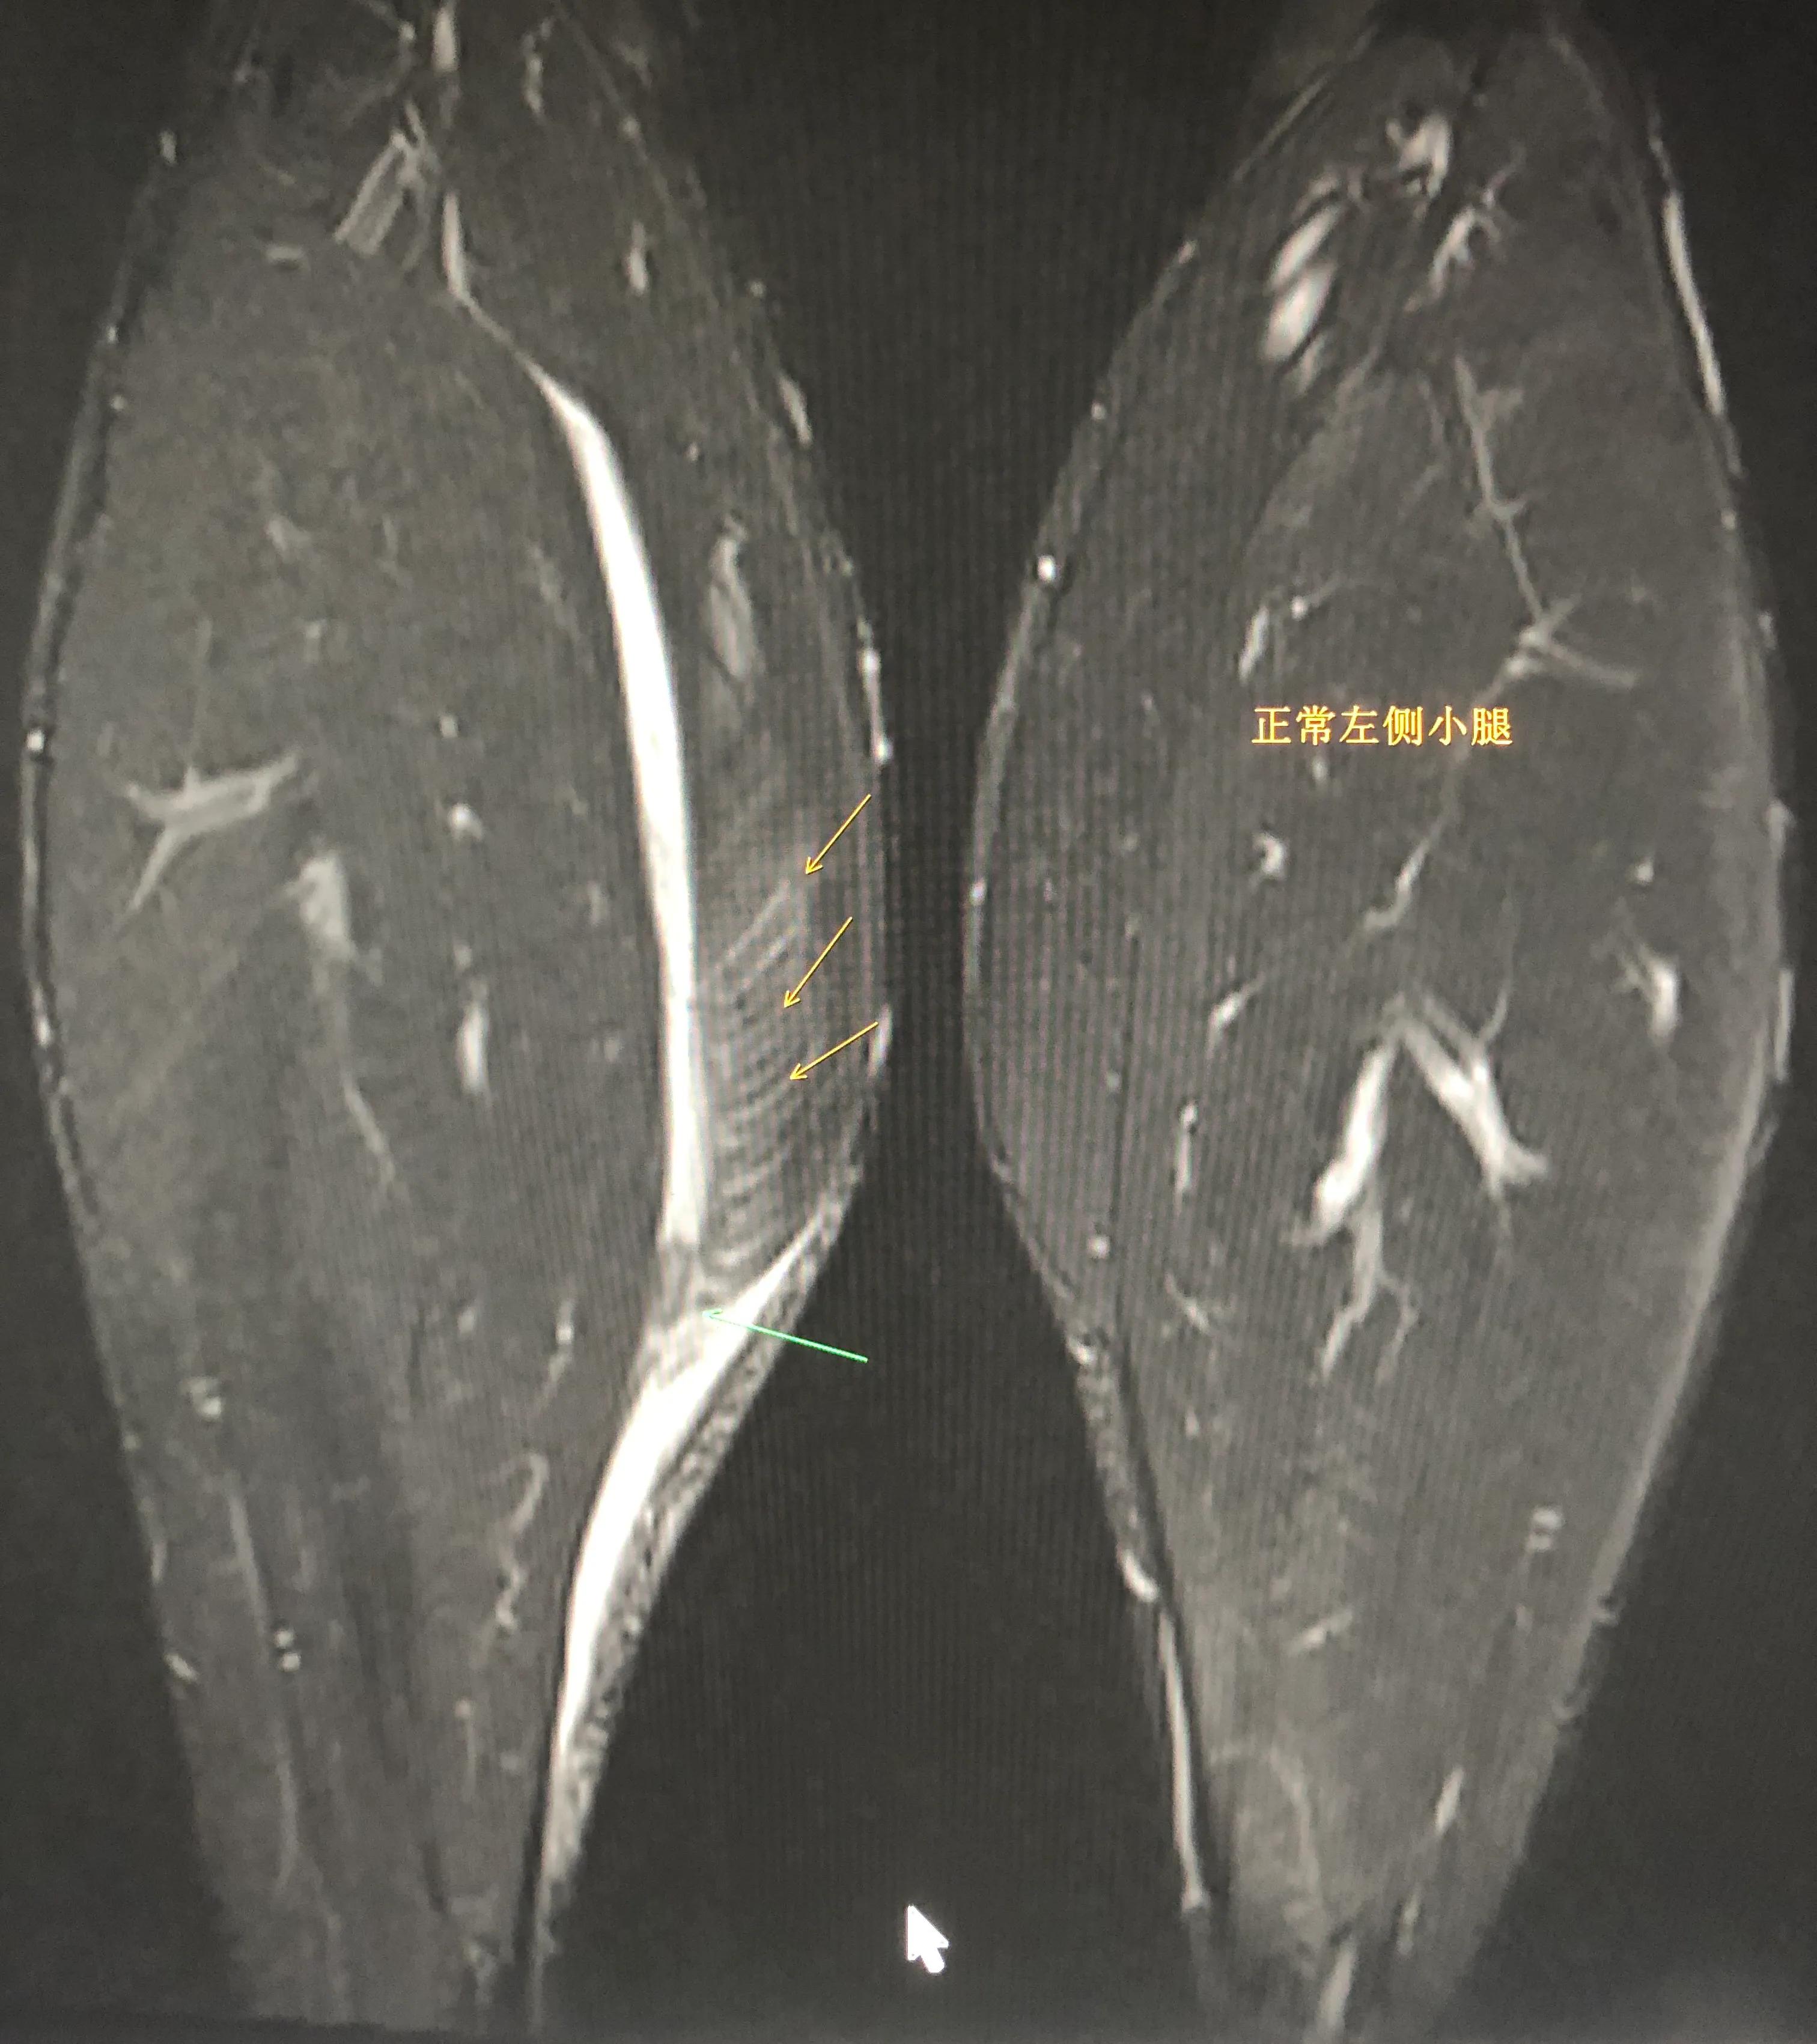

图2: 此例小腿肌肉发达。右侧腓肠肌大片撕裂(黄色箭头所示,对比一下左腿肌肉正常,没有那些白色的渗血;容易理解)。绿色箭头示肌腱断裂、轻度挛缩。